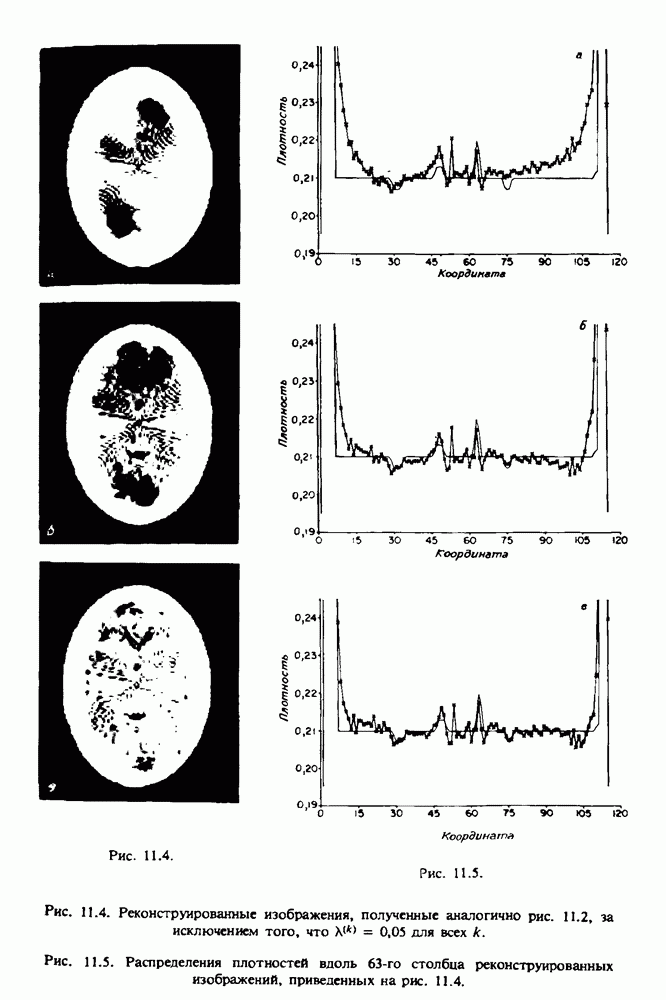

15.5. ЭКСПЕРИМЕНТАЛЬНЫЕ РЕЗУЛЬТАТЫ

Наш первый пример относится к случаю отображения системы желудочков головного мозга человека, которое было сделано по восьми смежным срезам толщиной На рис. 15.1 (вверху) приведены фрагменты из 80 х 80 элементов изображения трех из указанных срезов. Система желудочков изображена на фрагментах полностью. Размер элемента изображения в срезах составлял 1,5 х 1,5 мм, что соответствовало размеру элементарного

объема 1,5 х 1,5 х 8 мм, хотя более желательна, как и в предыдущих разделах, была бы кубическая форма элементарных объемов. Чтобы преобразовать элементарные объемы в кубические, использовалась линейная интерполяция данных для оценки 38 смежных срезов толщиной 1,5 мм. Таким образом, формируется массив из 80 х 80 х 32 чисел, характеризующих среднюю плотность множества элементарных объемов кубической формы.